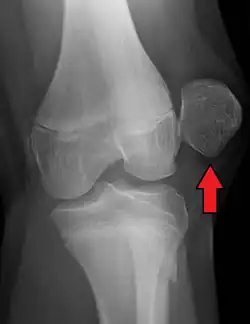

Displacement of the patella laterally out of its groove strains the medial stabilizing connective tissues, particularly the medial patellofemoral ligament (supporting 50–80% of the knee mechanisms in lateral patellar glide), which is torn usually at its femoral attachment.[3] Traumatic patellar dislocation may cause bleeding into the joint space, ligament and muscle attachment tearing, and fracture of the medial wing of the patella.[3] Fracture of the weight-bearing portion of the lateral femoral condyle occurs in 25% of traumatic patellar dislocations.[3] Surgical repair of the patellar stabilizing structures – the medial patellofemoral ligament and vastus medialis muscle – may be needed for athletes.[3]

| X-ray showing a patellar dislocation, with the patella out to the side. | |

A patellar dislocation is a knee injury in which the patella (kneecap) slips out of its normal position.[5] Often the knee is partly bent, painful and swollen.[1][2] The patella is also often felt and seen out of place.[1] Complications may include a patella fracture or arthritis.[3]